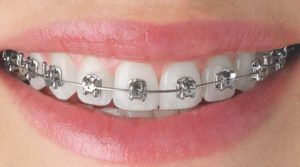

Orthodontics Department :

• Braces treatment formalaligned teeth

• Preventive treatment for tooth malalignment of child patient.